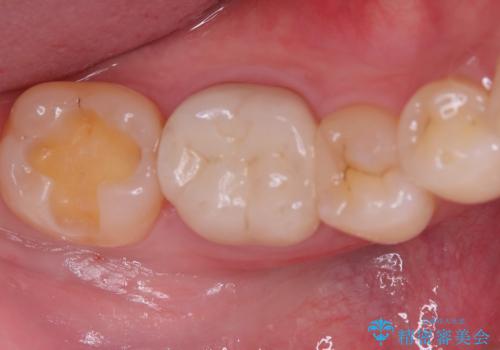

- 主訴:銀色の詰め物が取れてしまった。下の歯は笑うと見えるので、これを機に白くしたい。

保険適用のメタルインレーが脱離しており、歯冠色で審美性、適合性の良いセラミックインレーでのやり替えを提案しました。

メタルインレーが脱離した咬合面の窩洞内は、う蝕を除去し、セラミックインレーの厚みの担保とメタルタトゥー部分の除去を目的に形成を行いました。